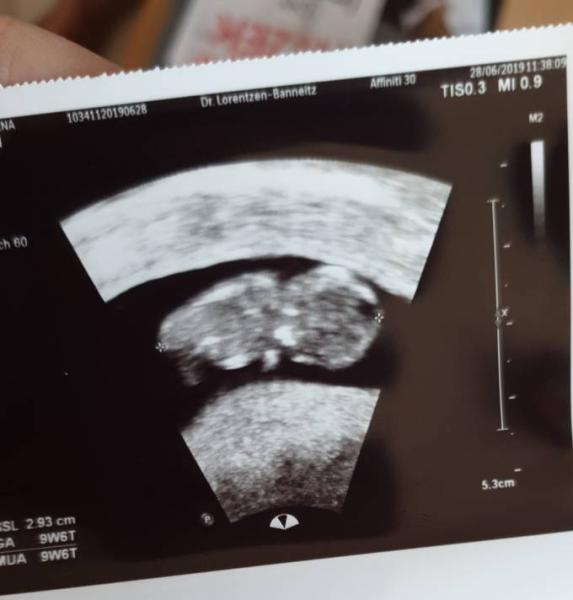

Hallo ihr lieben, auch ich bin noch dabei.. die Übelkeit und Müdigkeit lässt so allmählich nach ;) .. heute hatte ich wieder einen Termin zum Baby gucken und es ist alles super soweit .. jetzt heißt es wieder 4 Wochen warten bis ich wieder ein date mit dem Baby habe.. wie geht es euch so ? Wie kommt ihr mit der Hitze klar? LG

Bild zu 10.woche - Forum für Januar - Mamis